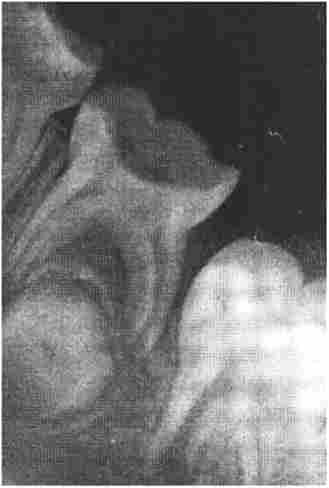

Дитина К., 6 років. Рентгенограма. Зуб 8.5 має каріозну порожнину, між країнами розташований фолікул постійного зуба

Мал. 1.11. Дитина К., 6 років. Рентгенограма. Зуб 8.5 має каріозну порожнину, між країнами розташований фолікул постійного зуба

Враховують вікові зміни. Периодонтальної щілину у дітей і підлітків ширше. Стінки кореневого каналу йдуть паралельно, розходяться у самої верхівки, утворюючи воронкообразное розширення, яке не слід приймати за кісту. Периодонтальної щілину видно тільки уздовж бічних стінок кореня. Цей стан триває приблизно один рік після прорізування зуба. Якщо корінь повністю не сформований, стінки кореневого каналу у верхівки не зімкнуті і видно верхівковий отвір (рис. 1.11), яке не простежується при повному формуванні кореня. Стадія формування верхівки кореня триває приблизно три роки.